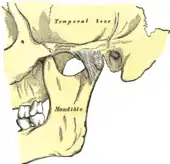

Temporomandibular joints

The temporomandibular joints are the dual articulation of the mandible with the skull. Each TMJ is classed as a "ginglymoarthrodial" joint since it is both a ginglymus (hinging joint) and an arthrodial (sliding) joint,[36] and involves the condylar process of the mandible below, and the articular fossa (or glenoid fossa) of the temporal bone above. Between these articular surfaces is the articular disc (or meniscus), which is a biconcave, transversely oval disc composed of dense fibrous connective tissue. Each TMJ is covered by a fibrous capsule. There are tight fibers connecting the mandible to the disc, and loose fibers which connect the disc to the temporal bone, meaning there are in effect 2 joint capsules, creating an upper joint space and a lower joint space, with the articular disc in between. The synovial membrane of the TMJ lines the inside of the fibrous capsule apart from the articular surfaces and the disc. This membrane secretes synovial fluid, which is both a lubricant to fill the joint spaces, and a means to convey nutrients to the tissues inside the joint. Behind the disc is loose vascular tissue termed the "bilaminar region" which serves as a posterior attachment for the disc and also fills with blood to fill the space created when the head of the condyle translates down the articular eminence.[37] Due to its concave shape, sometimes the articular disc is described as having an anterior band, intermediate zone and a posterior band.[38] When the mouth is opened, the initial movement of the mandibular condyle is rotational, and this involves mainly the lower joint space, and when the mouth is opened further, the movement of the condyle is translational, involving mainly the upper joint space.[39] This translation movement is achieved by the condylar head sliding down the articular eminence, which constitutes the front border of the articular fossa.[28] The function of the articular eminence is to limit the forwards movement of the condyle.[28] The ligament directly associated with the TMJ is the temporomandibular ligament, also termed the lateral ligament, which really is a thickening of the lateral aspect of the fibrous capsule.[28] The stylomandibular ligament and the sphenomandibular ligament are not directly associated with the joint capsule. Together, these ligaments act to restrict the extreme movements of the joint.[40]